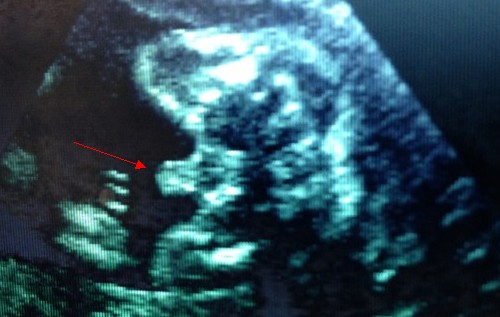

23周男寶B超圖,小jj辣么明顯。

但是偶爾也會(huì)有翻盤的時(shí)候(B超是女,生下來(lái)是男?;蛘邉偤孟喾矗?,準(zhǔn)確率95%。